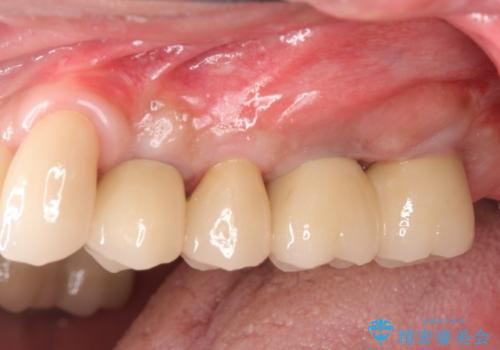

骨の造成を行った上顎インプラント治療

骨の造成を行ったことで歯肉のラインは平らになり、清掃性の高い歯周環境を作り出すことができました。